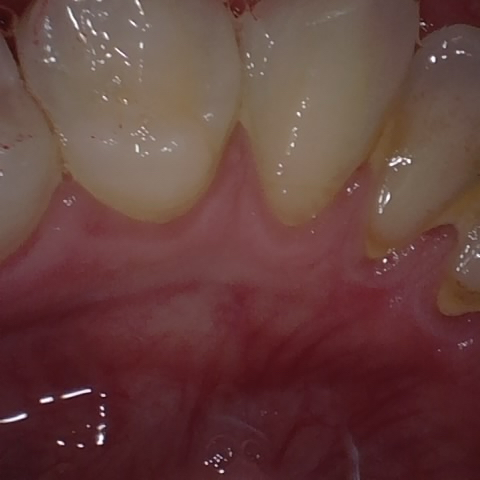

Annotated as "Good"